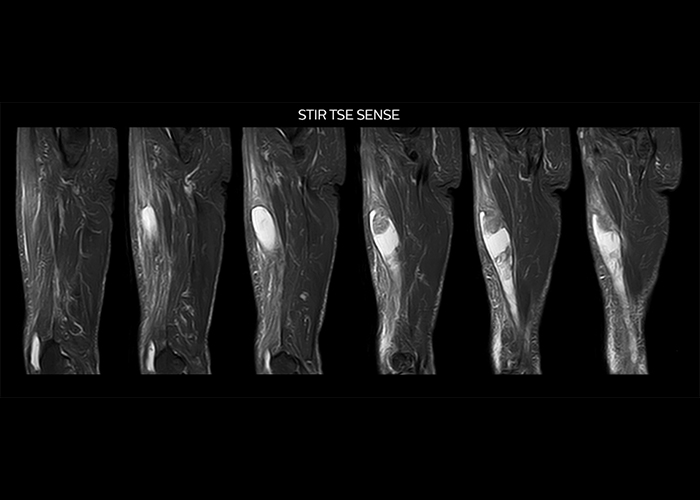

“On average, we scan about 80 patients per day, but on some days we scan well over 100 patients. The scanner is in use 7 days per week, operated 20 hours per day on week days and 8 hours per day in the weekend,” Mr. Tuna says. “To avoid coil changes we plan examinations of similar anatomies back to back, such as head and spine. Multiva helps us here a lot because coils don’t need to be changed frequently. Moreover, thanks to parallel imaging technology and 16-channel HeadSpineTorso and 8-channel MSK coils we are able to achieve excellent image quality. In this way Multiva helped us to increase both image quality and productivity.” “Neurological cases, such as brain and spine imaging, represent the largest share in our MR scanning, followed by musculoskeletal cases. In general, we use simple and basic imaging protocols. But occasionally, we use advanced techniques for problematic cases if necessary.

“Since we have Multiva, we have improved our workflow, because it has been so easy for our operators to learn and use Multiva. Our operators notice that the coils are lightweight and coils don’t need to be changed frequently. The user interface is easy to use. Features like this help us to scan a high number of patients. For instance, the musculoskeletal coils can be used interchangeably, and due to the user-friendly interface, the number of mistakes such as, for example, correct coil element selection has decreased significantly, because the system does it automatically by itself.” “Most important, Multiva satisfies our clinical imaging needs very well,” says Mr. Tuna. “Many features of Multiva have become similar to the Ingenia system. Even in more complex imaging such as abdominal and cardiac, the image quality and performance of Multiva is better than we expected. General surgeons and physicians from our hospital’s internal medicine department prefer to refer to us because of this.”